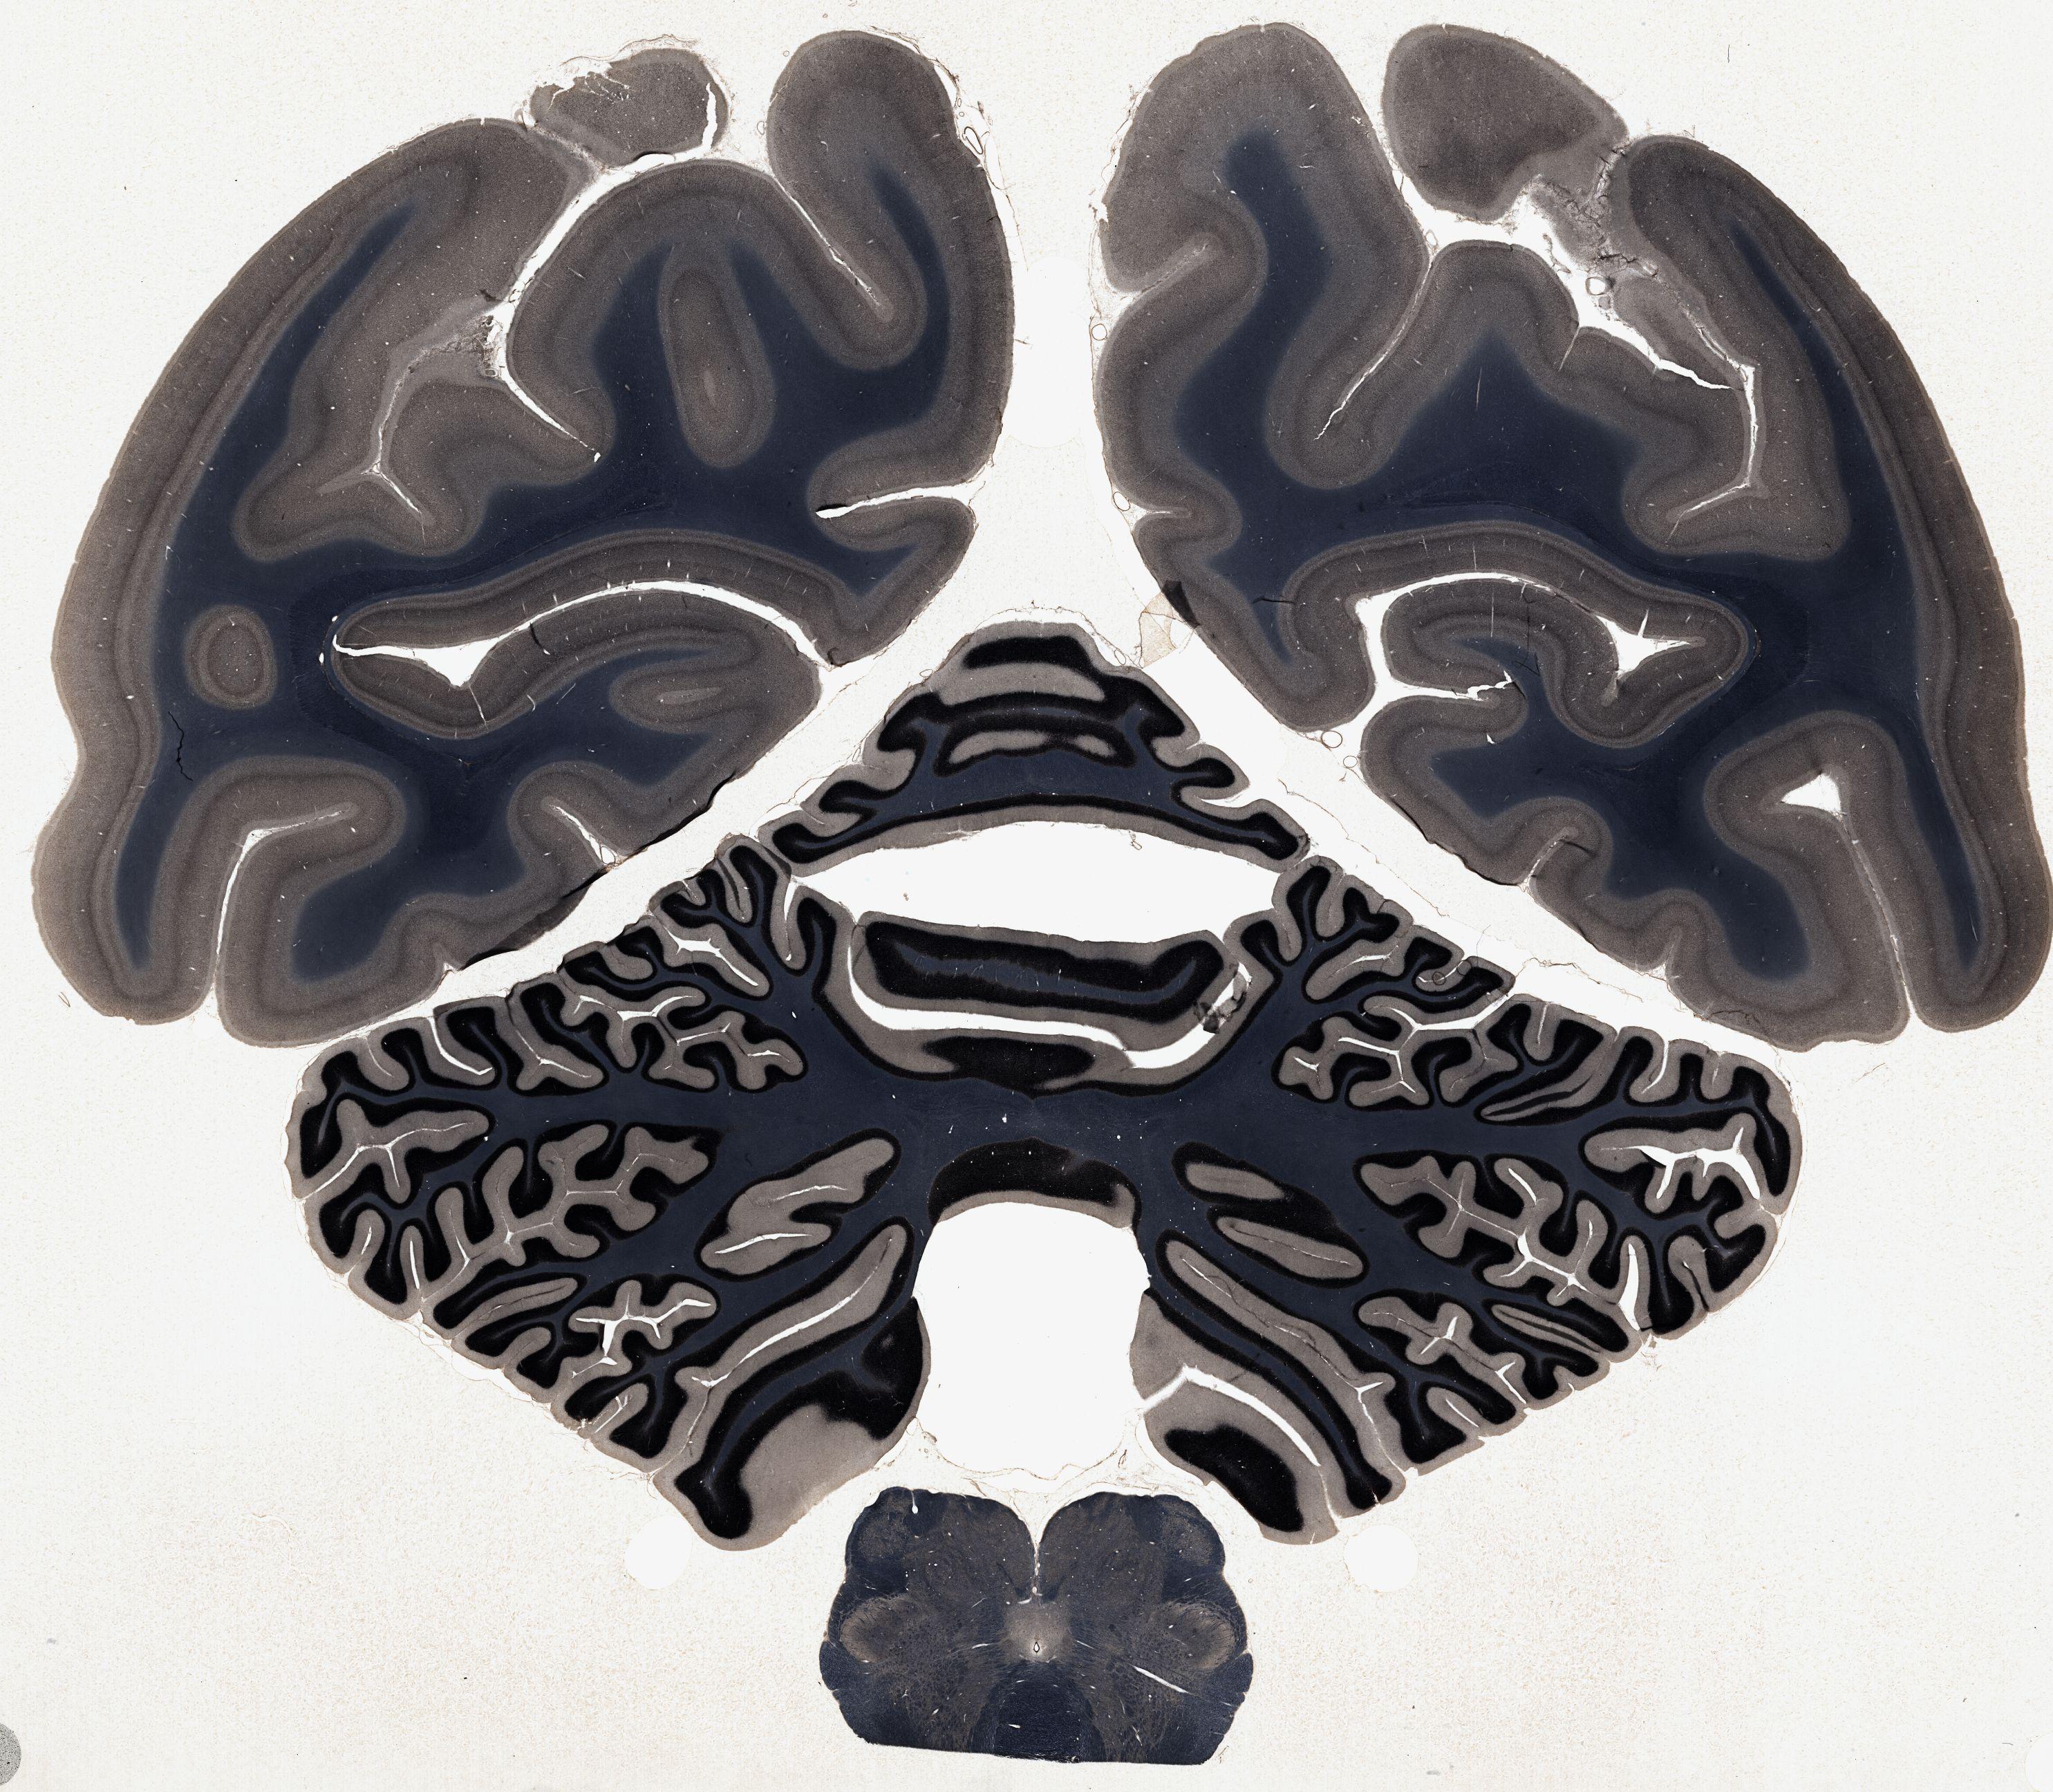

Datasets -> Macaca Mulatta -> Weil, coronal, histo, Whole-Brain, adult

[ Metadata ]   ·   Source: NeuroScience Associates

Displaying Sections 1 thru 36 of 36 Sections for this Dataset